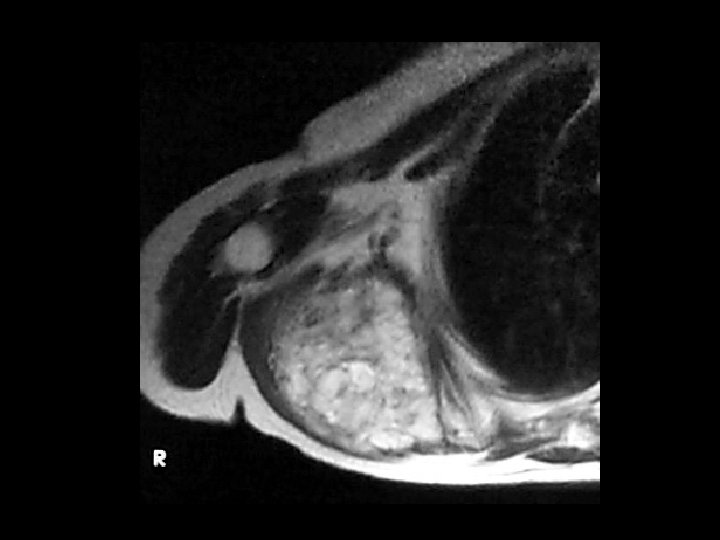

Chondrosarcoma • Findings: – Large bone-forming soft tissue mass centered in the right SI joint – “ring and arc Ca 2+” = calcified chondroid matrix • ddx: – NONE! – This is an Aunt Minnie!